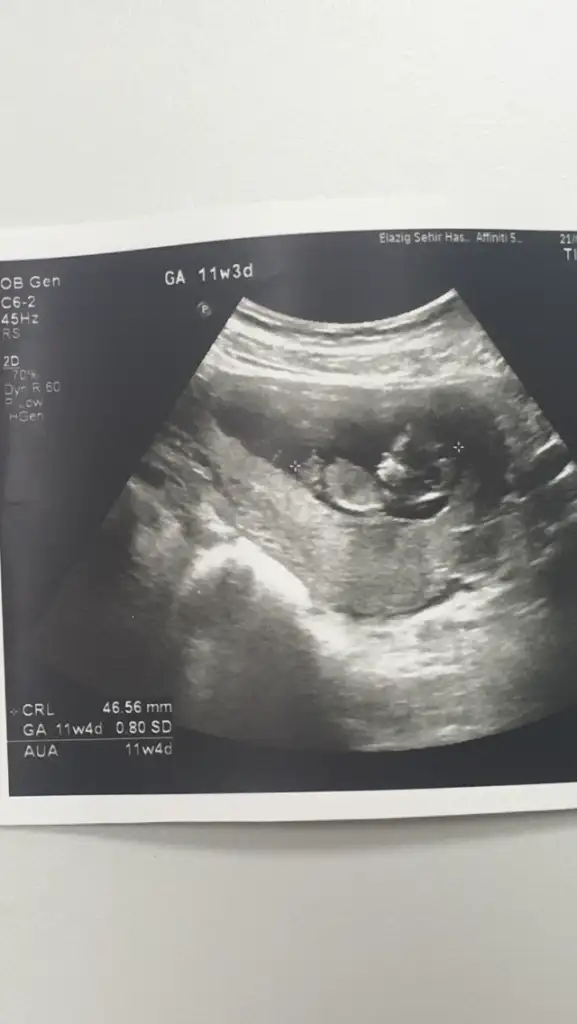

Erkek mi dediBana da yorum yaparmısınız lütfen. Bugün geldim doktordan. Cinsiyeti söyledi ama kesin olarak bi ay sonra dedi

Çünkü kordonu pipi sanma ihtimalleri varKız dedi ama kesin sonucu bir sonraki randevuda söylicem dedi. Ama emindir bence.14+3 sonuçta. Daha nezaman kesinleşir ki. Değişme ihtimali varmıdır ?

Bir tomurcuk var sanki erkek olabilir yinede USG istiyorum net değil birde 11 hafta değil sanirimBiseye benzetemedim

10+3 11 satılıyor diye attim ama garanti olsun diye sana 12+5 de felan gelcemBir tomurcuk var sanki erkek olabilir yinede USG istiyorum net değil birde 11 hafta değil sanirim

Erkek gibi ama tekrar USG istiyorumSelamIkra meyra banada yorum yapabilirmisin 11+3 teyiz Ikra meyra

12 haftalığa göre çok net göstermiş masallahUSG 12.3 şimdi 17 haftalik